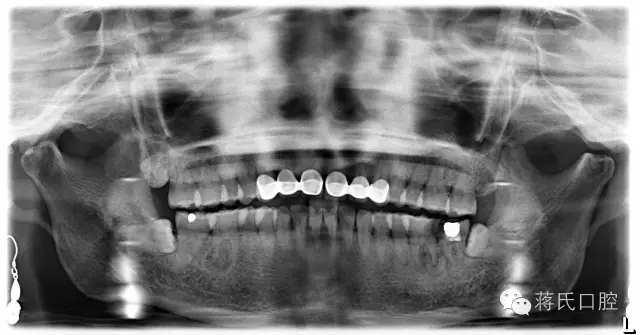

術(shù)前檢查:全景片顯示左下六七殘冠并發(fā)根尖炎癥,骨量豐滿、骨高度良好、但因?yàn)闅埞跁r(shí)間較長(zhǎng),對(duì)合牙伸長(zhǎng),咬合距離低,建議患者正畸治療上牙,但患者拒絕。因?yàn)榛颊呤墙處熉殬I(yè)所以在設(shè)計(jì)方案及治療溝通中詳細(xì)醫(yī)囑,每次治療均經(jīng)過患者同意后操作。

種植前全景片